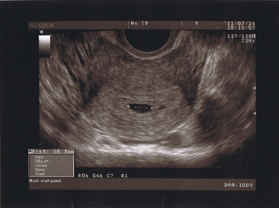

El punto negro es mi útero, y dentro, el anillo de poder, jajajaja usease, el embrionario 😛

Ella me hizo una eco intravaginal, y ¡ahí estaba! un diminuto anillo embrionario y mi útero de 1cm. No entendía ni jota de lo que me estaba contando (menos mal que iba señalando en la pantalla..), así que mi chico y yo asistíamos atónitos ante aquello que era suyo y que era mío. ¡Que fuerte!